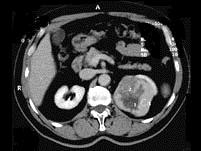

问题 男,65岁,左侧腰背部胀痛伴无痛性全程血尿3个月余,CT平扫及增强检查如图所示,下列说法正确的是 ( )

选项 A、考虑为左侧肾癌 B、考虑为左侧肾错构瘤 C、增强扫描肾皮质期可见肿块明显强化,其内亦有无强化区 D、增强扫描肾实质期可见肿块强化迅速下降,但密度比平扫时仍要高 E、平扫时见左肾上极有一软组织肿块影,其边界较清楚

答案 ACDE